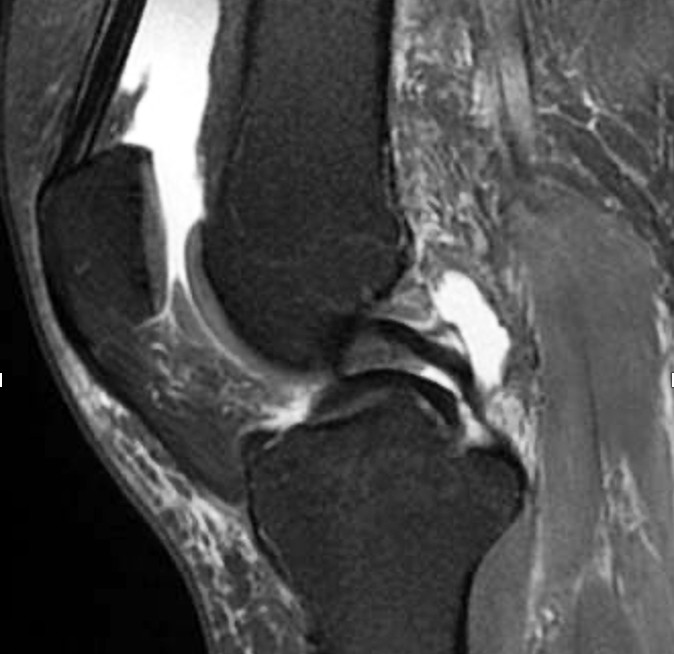

However, degenerative meniscus tears can often be asymptomatic and may appear as incidental findings on MRI without clinical significance (20). The tears occur in degenerate tissue with reduced water content, fewer elastic fibres and increased stiffness, such that an axial load gives rise to shear forces that tear the connections between collagen fibres. The shape of the meniscus changes and its protective function in relation to the articular cartilage is reduced (21). The tears are described as complex (multiple tears), horizontal (Figure 1) or oblique (flap tears), and most often occur in the posterior part of the medial meniscus.

Traumatic meniscus injuries are most often seen in active younger individuals and are often high-energy injuries, not infrequently associated with damage to the anterior cruciate ligament (23). Typical traumatic tears are 'bucket handle'-shaped (longitudinal, vertical (Figure 2, Figure 3), and with the torn part of the meniscus potentially folded over towards the intercondylar eminence), radial, or flap-shaped. Folded bucket-handle tears can restrict both flexion and extension, and early repositioning and suturing are indicated to prevent shrinkage and destruction of the meniscus tissue.

Meniscal root tears are injuries at the site of or close to the posterior attachment of the menisci to the tibia (posterior root tears) (Figure 2) (24). Medial root tears are most often seen in degenerative knees as part of the development of osteoarthritis, and lateral root tears are most often seen in younger patients with damage to the anterior cruciate ligament. Root tears often cause more pain and effusion than other meniscus injuries.